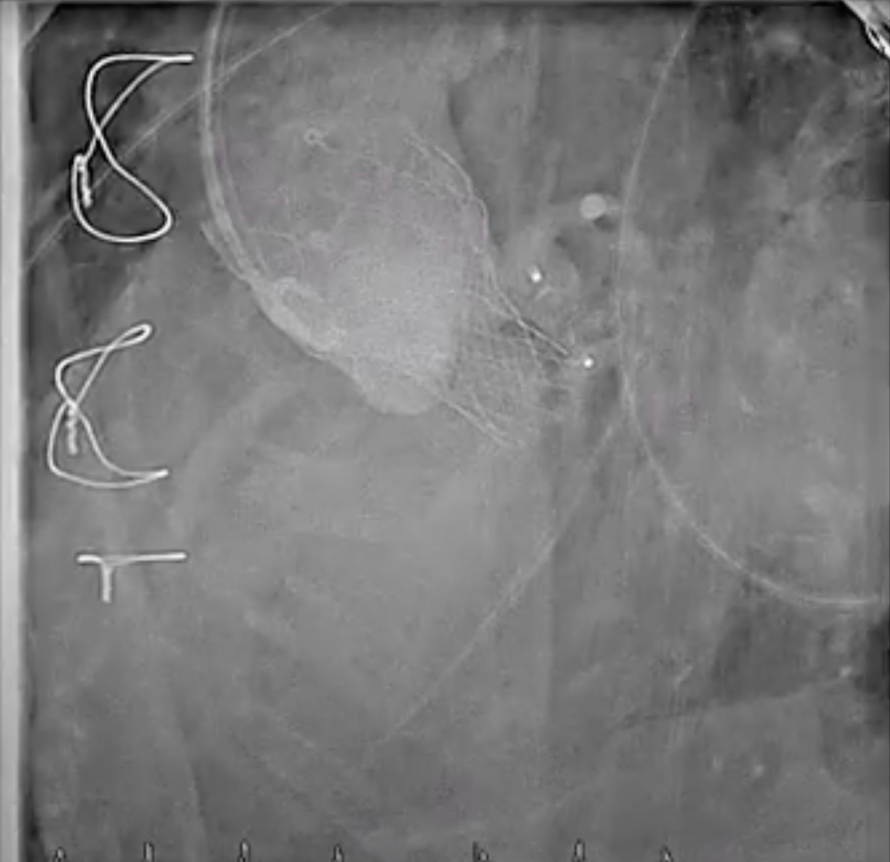

Under local anesthesia, the RFA was punctured, and a 6-Fr sheath was introduced. A 6-Fr pigtail catheter over a 0.035-inch J-tip wire was advanced into the ascending aorta, and an aortogram demonstrated a moderate PVL originating from the surgical valve ring and the aortomitral curtain.The pigtail catheter was replaced with a 6-Fr MPA2 catheter to delineate the anatomy of the transcatheter heart valves and PVL. A 6-Fr JL 3.5 catheter was then used for a nonselective left coronary angiogram, confirming the PVL adjacent to the aortic annulus. A Terumo guidewire was advanced through an Amplatz Left (AL1) catheter and successfully crossed the PVL into the left ventricle (LV).For device delivery, the LFA was also punctured, and a 6-Fr sheath was inserted. A pigtail catheter was placed in the ascending aorta to identify the left main ostium. Attempts to advance an AGA Amplatzer Vascular Plug (AVP) 10/7 mm through the PVL were made using multiple guiding systems, including AL and JR4 catheters, a 6-Fr Shuttle sheath, and a Superstiff 0.035-inch wire, but initial passage into the LV was unsuccessful.Balloon sizing was performed using a Boston Scientific Mustang balloon (4.0 mm ¡¿ 20 mm ¡¿ 75 cm) inflated to 4 atm. The 6-Fr sheath was exchanged for a 7-Fr sheath, and a 7-Fr Boston MP 90-cm guiding catheter was advanced into the LV. An AGA Amplatzer Vascular Plug 10/7 mm was successfully deployed across the PVL. Final aortography confirmed successful occlusion of the PVL.

Final (5_17 angio).mp4

Case Summary